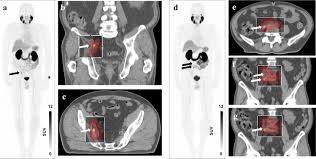

Semiautomatically Quantified Tumor Volume Using 68ga Psma 11 Pet As A Biomarker For Survival In Patients With Advanced Prostate Cancer Journal Of Nuclear Medicine

Semiautomatically Quantified Tumor Volume Using 68ga Psma 11 Pet As A Biomarker For Survival In Patients With Advanced Prostate Cancer Journal Of Nuclear Medicine from jnm.snmjournals.org